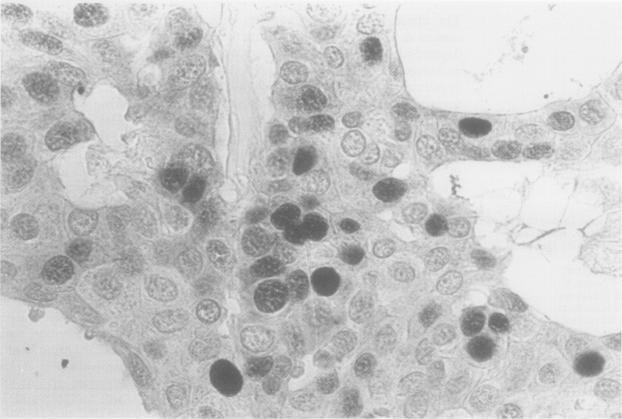

A monoclonal antibody PC10 was applied to formalin fixed, paraffin wax embedded tissue in 144 cases of primary breast cancer. PCNA immunostaining was scored by counting 1000 cells; the percentage of positive stained cells was recorded as the PCNA labelling index (PCNA-LI).

将单克隆抗体PC10应用于144例原发性乳腺癌的福尔马林固定、石蜡包埋组织。通过计数1000个细胞对PCNA免疫染色进行评分;将阳性染色细胞的百分比记录为PCNA标记指数(PCNA-LI)。